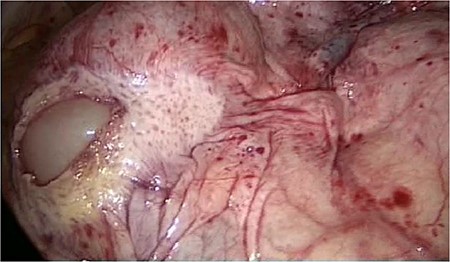

The laparoscopic anterior resection was performed in February 2019. The patient was positioned in a modified lithotomy position. The pneumoperitoneum was established by a Veress needle. The trocars were placed umbilical, two on the left and one on the right abdominal wall. The descending colon and the endoscopic ink-marked region were visualized perfectly. While getting an overview of the abdominal cavity, we noticed an abnormality in the ileum region. It seemed that the peritoneum was covering the entire ileum. The situs is depicted in Figs 1–4.

On the left side, we show the retroperitoneal pancreas, with the (as well) retroperitoneal jejunum on the right side.

The entire small bowel was found retroperitoneal covered by a slim peritoneal layer (Fig. 1). The dorsal peritoneum covering the ileum was opened (Fig. 2).